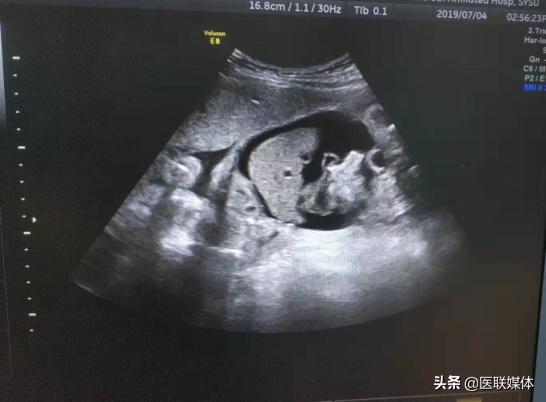

正当她在进行三维B超检查时,被告知胎儿心包积液及胎儿腹腔积液,这道晴天霹雳把全家人一下打懵了。随着孕周的增加,胎儿宫内水肿一次比一次严重,孕26+周时进行脐带血穿刺后胎儿血红蛋白仅23g、心包积液、腹腔胸腔积液、全身水肿,而钟女士也出现了全身水肿的镜像综合症。情况万分紧急,胎儿随时都会在宫内死亡。

宫内输血是在实时动态的超声引导下,穿刺胎儿的细小脐静脉,术前需要精确计算输血量,输血速度,术后需要监测和处理感染、心动过缓,脐带血肿等并发症,从而改善胎儿宫内状态并尽量延长孕周。而国内目前仅少数胎儿医学中心能开展此技术。要求高、难度大,但为了挽救宝宝的生命,无论如何也要拿下此关。

尽管第一次手术成功,大家依旧要面临更残酷的考验。由于母胎MN血型不合,需要多次输血才能维持。随后分别四次输入O型RhD阳性NN型浓缩红细胞悬液共196ml。并于7月23日行胎儿腹腔穿刺,抽出淡黄色腹腔积液97ml,多次查胎儿血流动力学示胎儿大脑中动脉PSV情况好转,B超胎儿腹水胸腔积液减少。

但病魔对于大家的挑战仍未结束,新生儿出生后呼吸微弱,心率慢,腹部膨隆,全身明显水肿。医务人员立即予气管插管接复苏囊加压给氧及在床旁B超引导下行腹腔穿刺抽液术,待生命体征较平稳后在气管插管连接复苏囊状态下转新生儿科进一步治疗。